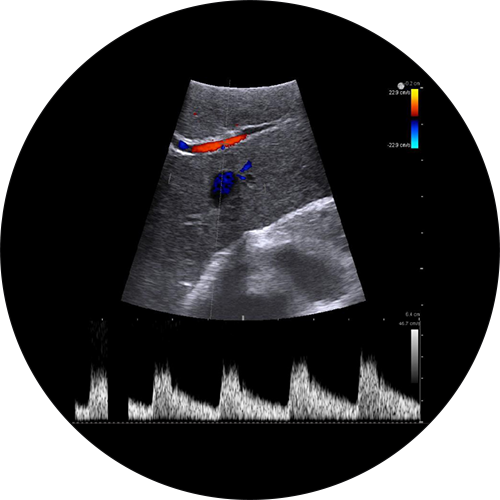

Liver metastatic lesion with color Doppler, visualized with Laparoscopic Transducer